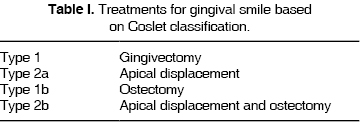

49 year old female patient referred by the Prosthetics Department of the Graduate School, National School of Dentistry, National University of Mexico UNAM. Diagnosis emitted was clinically shortened crowns due to bruxism, mal-adjusted restorations in upper centrals, with caries recurrence (Figure 2a). Upon first inspection the following was observed: temporomandibular articulation (TMA) presented crepitation of the right condyle; when performing opening movements, there was deviation to the left side of the lower jaw. There was malpositioning of teeth in the lower arch. The patient complained about having ''short teeth'' and wanted to correct them.

Clinical assessment revealed excessive gingival exposition and clinically shortened crowns in teeth numbers 15, 14, 13, 11, 21, 22, 23, 24 and 25, as well as irregular gingival margin. X rays analysis revealed suitable crown-root ratio (Figure 2b) as well as suitable height of bone crests. Probing did not reveal periodontal pockets, nevertheless, there was bleeding in certain locations. Due to all the aforementioned factors, periodontal diagnosis emitted was localized gingivitis, with delayed passive eruption. Treatment was therefore crown lengthening procedures with tooth bone surgery 15 to 25 (Figure 2c).